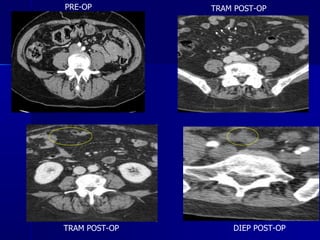

PRE-OP DIEP POST-OP TRAM POST-OP TRAM POST-OP

PRE-OP DIEP POST-OPTRAM POST-OP TRAM POST-OP